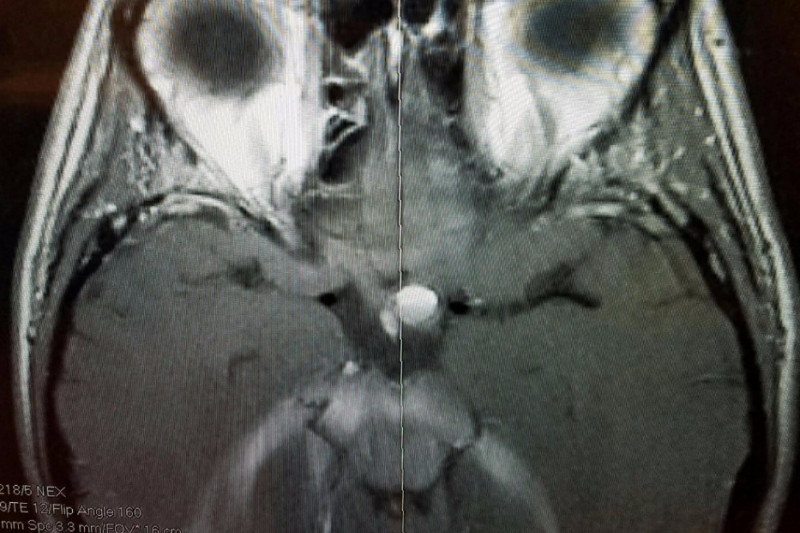

Hi my name is Monte. The pic you see is from the MRI of my sister Tina's head. The white circle in the center of the pic is what the Dr's think is a blood clot, but won't know for sure until they do surgery. For the last month she has been loosing sight in her one eye because it has been putting pressure on her optic nerve. It took multiple tests, and appointments with different specialists to figure out what was causing her to loose sight. The Dr's initially said it was a lesion on her brain, but didn't know exactly what was causing it. It could have been caused from a disease, trauma, or a tumor. Fortunately they don't think it is any of those things, but won't know for sure until they do surgery.  She goes in this Wednesday on November 30th to have surgery were the Dr's will have to open up her skull to remedy the issue. They aren't sure if her full sight will return. My sister Tina is a single mom of two, who works two jobs already just to try to make ends meet. Thankfully she has insurance through her work that will cover 80%, but she will have to pay the other 20%.  I don't know exactly how long she will be out of work to recover, but the money raised will go towards her medical bills and loss of income due to not being able to work. Honestly I dont know if the goal amount will be enough if it is reached, but anything will help.